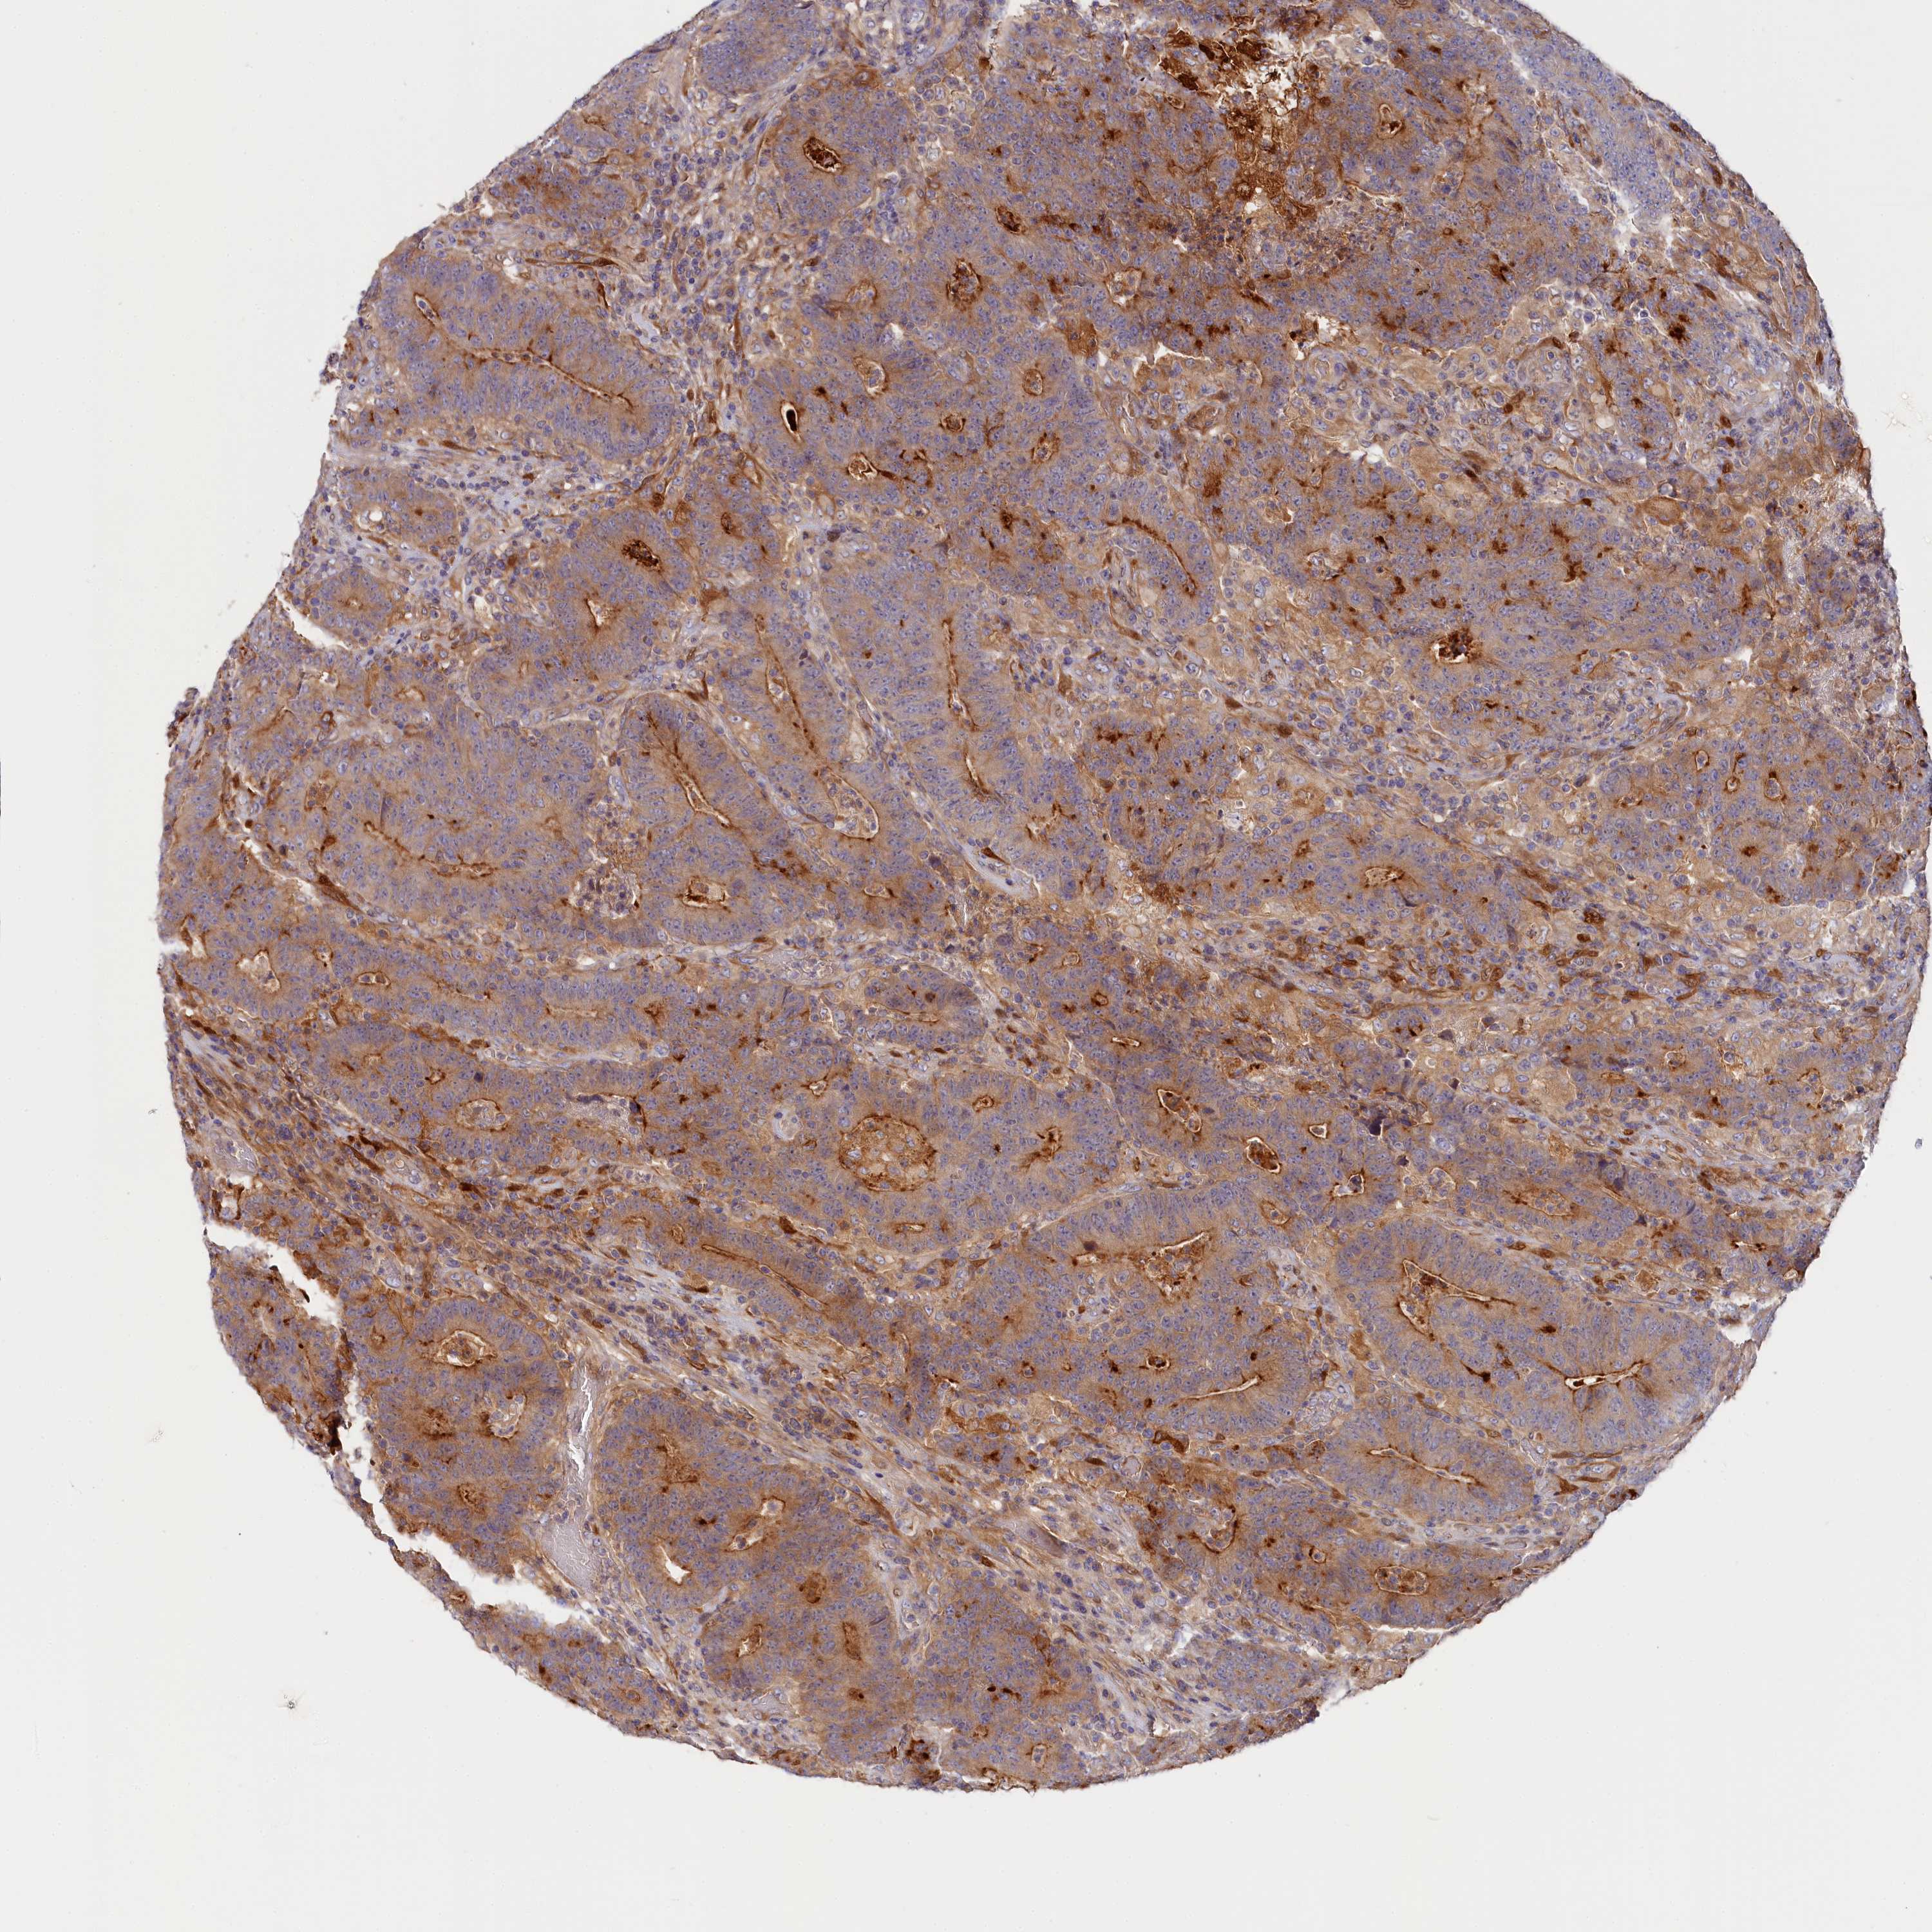

CANCER COLORECTAL CANCER Show tissue menu

Colorectal cancer

Human cancer

Colon adenocarcinoma